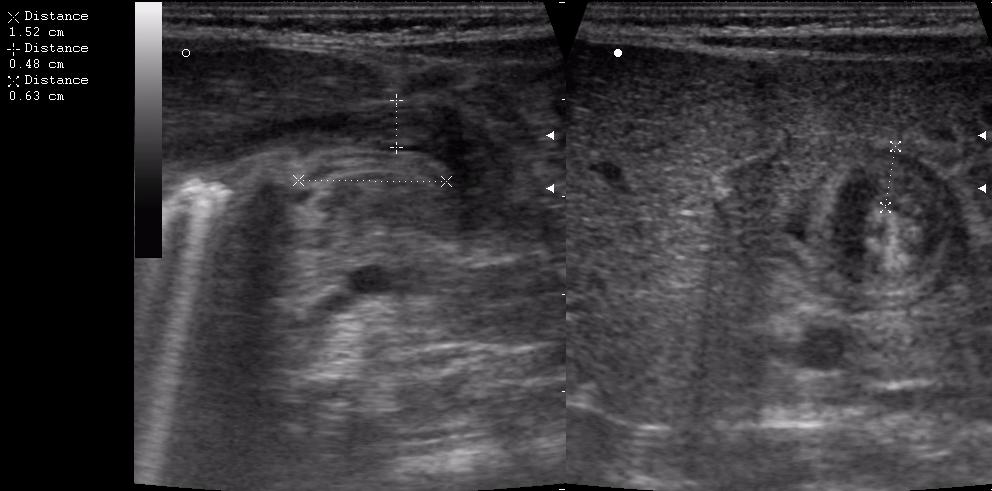

а у нас сегодня опять одна красава! (месяца 3 НИОДНОГО пилоростеноза небыло!)

сорри, колесико недотянула

Признак "пончика".

А что, похоже.